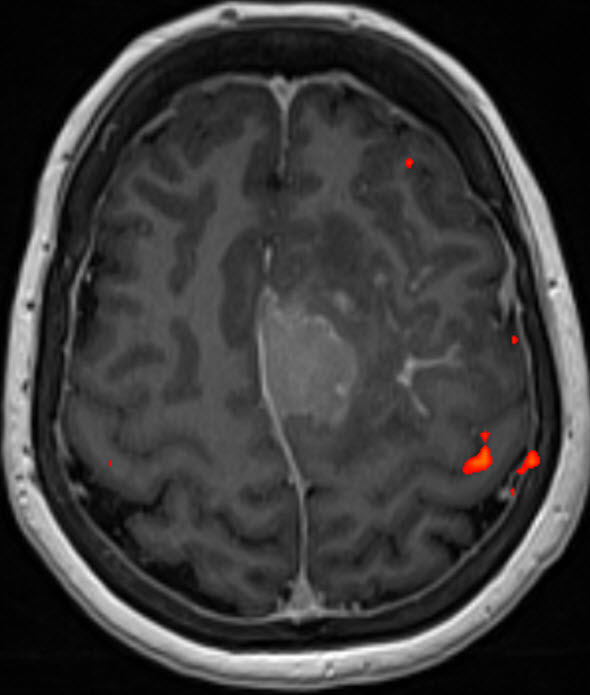

The patient was sent for investigations  with complete protocol of MRI with clinical applications, including fMRI, which were done 12-November-2019 showing huge meningioma occupying both parietal areas more the left with involvement of the falx cerebri  and tumor was extending inside the mid third of the SSS with draining veins anterior and posterior to the involved SSS. The motor area was located posterior to the lesion. The patient was sent for cardio evaluation.

Fig-1: fMRI of the right hand tapping.